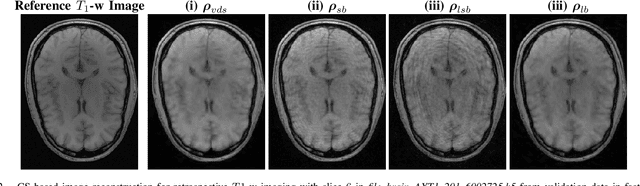

Abstract:Compressed sensing (CS) in Magnetic resonance Imaging (MRI) essentially involves the optimization of 1) the sampling pattern in k-space under MR hardware constraints and 2) image reconstruction from the undersampled k-space data. Recently, deep learning methods have allowed the community to address both problems simultaneously, especially in the non-Cartesian acquisition setting. This paper aims to contribute to this field by tackling some major concerns in existing approaches.Regarding the learning of the sampling pattern, we perform ablation studies using parameter-free reconstructions like the density compensated (DCp) adjoint operator of the nonuniform fast Fourier transform (NUFFT) to ensure that the learned k-space trajectories actually sample the center of k-space densely. Additionally we optimize these trajectories by embedding a projected gradient descent algorithm over the hardware MR constraints. Later, we introduce a novel hybrid learning approach that operates across multiple resolutions to jointly optimize the reconstruction network and the k-space trajectory and present improved image reconstruction quality at 20-fold acceleration factor on T1 and T2-weighted images on the fastMRI dataset with SSIM scores of nearly 0.92-0.95 in our retrospective studies.

Abstract:The SPARKLING algorithm was originally developed for accelerated 2D magnetic resonance imaging (MRI) in the compressed sensing (CS) context. It yields non-Cartesian sampling trajectories that jointly fulfill a target sampling density while each individual trajectory complies with MR hardware constraints. However, the two main limitations of SPARKLING are first that the optimal target sampling density is unknown and thus a user-defined parameter and second that this sampling pattern generation remains disconnected from MR image reconstruction thus from the optimization of image quality. Recently, datadriven learning schemes such as LOUPE have been proposed to learn a discrete sampling pattern, by jointly optimizing the whole pipeline from data acquisition to image reconstruction. In this work, we merge these methods with a state-of-the-art deep neural network for image reconstruction, called XPDNET, to learn the optimal target sampling density. Next, this density is used as input parameter to SPARKLING to obtain 20x accelerated non-Cartesian trajectories. These trajectories are tested on retrospective compressed sensing (CS) studies and show superior performance in terms of image quality with both deep learning (DL) and conventional CS reconstruction schemes.